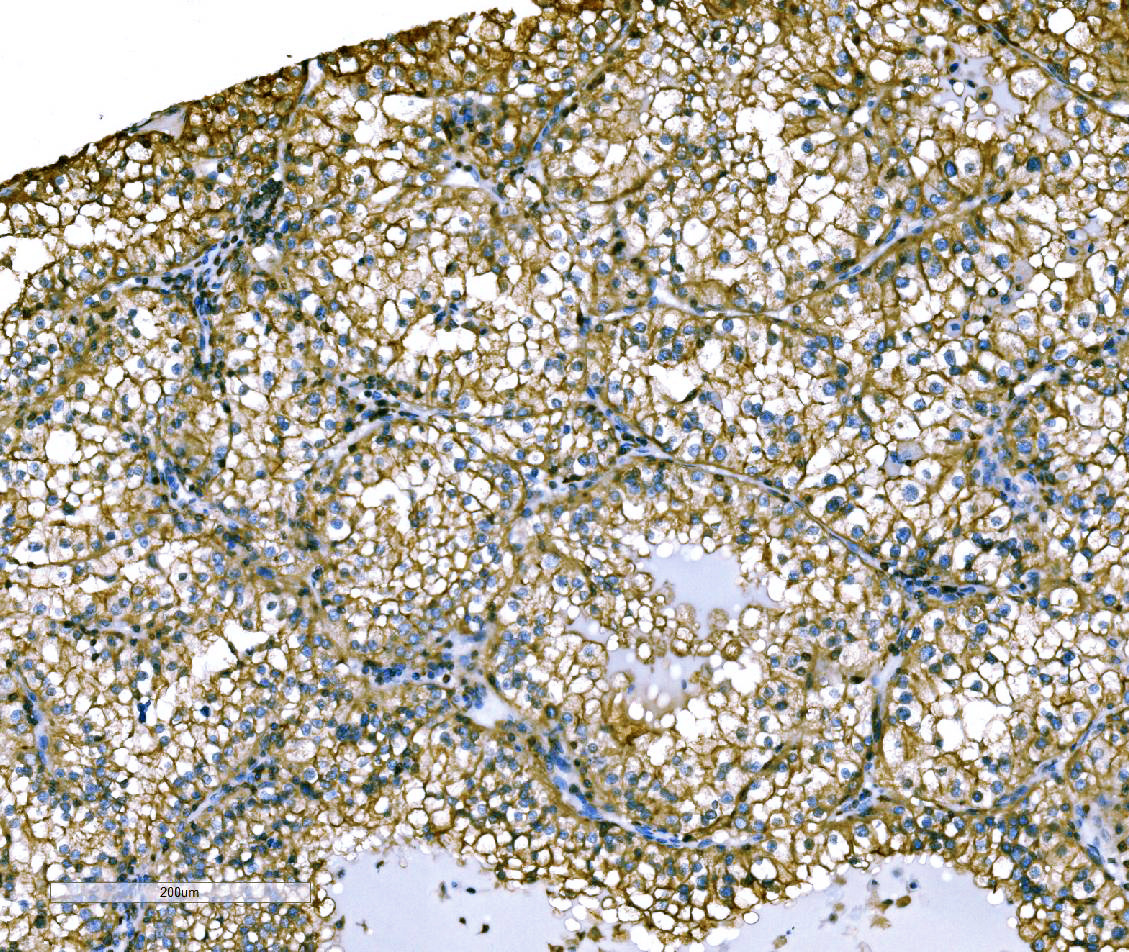

IHC analysis of Ezrin/EZR using anti-Ezrin/EZR antibody (A01750-2).

Ezrin/EZR was detected in a paraffin-embedded section of human renal cell carcinoma tissue. Biotinylated goat anti-rabbit IgG was used as secondary antibody. The tissue section was incubated with rabbit anti-Ezrin/EZR Antibody (A01750-2) at a dilution of 1:200 and developed using Strepavidin-Biotin-Complex (SABC) (Catalog # SA1022) with DAB (Catalog # AR1027) as the chromogen.